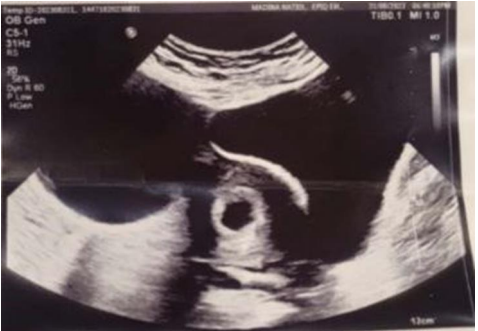

Anteverted gravid uterus, shows a single healthy pregnancy sac, with a healthy decidual reaction, it contains a single viable focal node with regular cardiac pulsations. RI 18mm-8 weeks 3days+/- 7 days Figure (1).

Fig 1, Fig 2

Figure 1